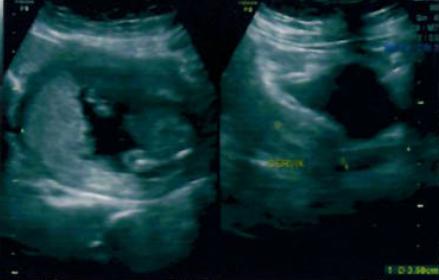

16 W imagesAttachment 28068Attachment 28069

I think girl as I can't see anything on this potty shot xxx

Maybe girl!

hi how do u predict? Bcos in first pic I could see a nub pointing upwards?? Could anyone clarify??